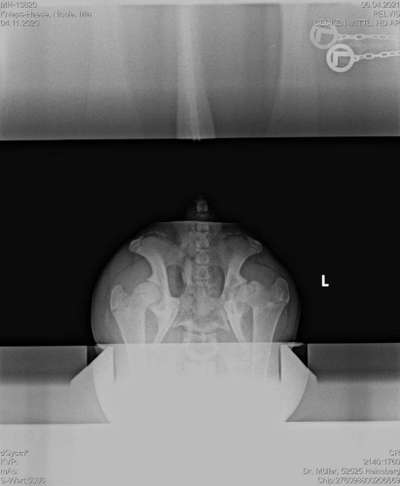

Das Röntgenbild meiner Hündin.

Das Röntgenbild zeigt alterstypisch noch deutliche Wachstumsfugen.

Im Bereich des linken Hüftgelenkes ist sowohl eine Aufhellung der Beckenpfanne sichtbar als auch eine Fraktur entlang der Wachstumsfuge des linken Femurkopfes (Epiphysiolysis proximalis ossis femoris).

Beim Versuch diese konservativ zu behandeln, kann es aufgrund der bereits vorhandenen Beteiligung der Beckenpfanne zu einer frühen Arthrose oder auch Gelenksversteifung kommen.

Es ist eine Stufe im Oberschenkelkopf durch die Ablösung sichtbar, welche den arthrotischen Prozess beschleunigen könnte.